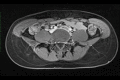

Fig. 4a:

MRI of 18 year-old women showing compression and thrombotic occlusion of the left iliac vein